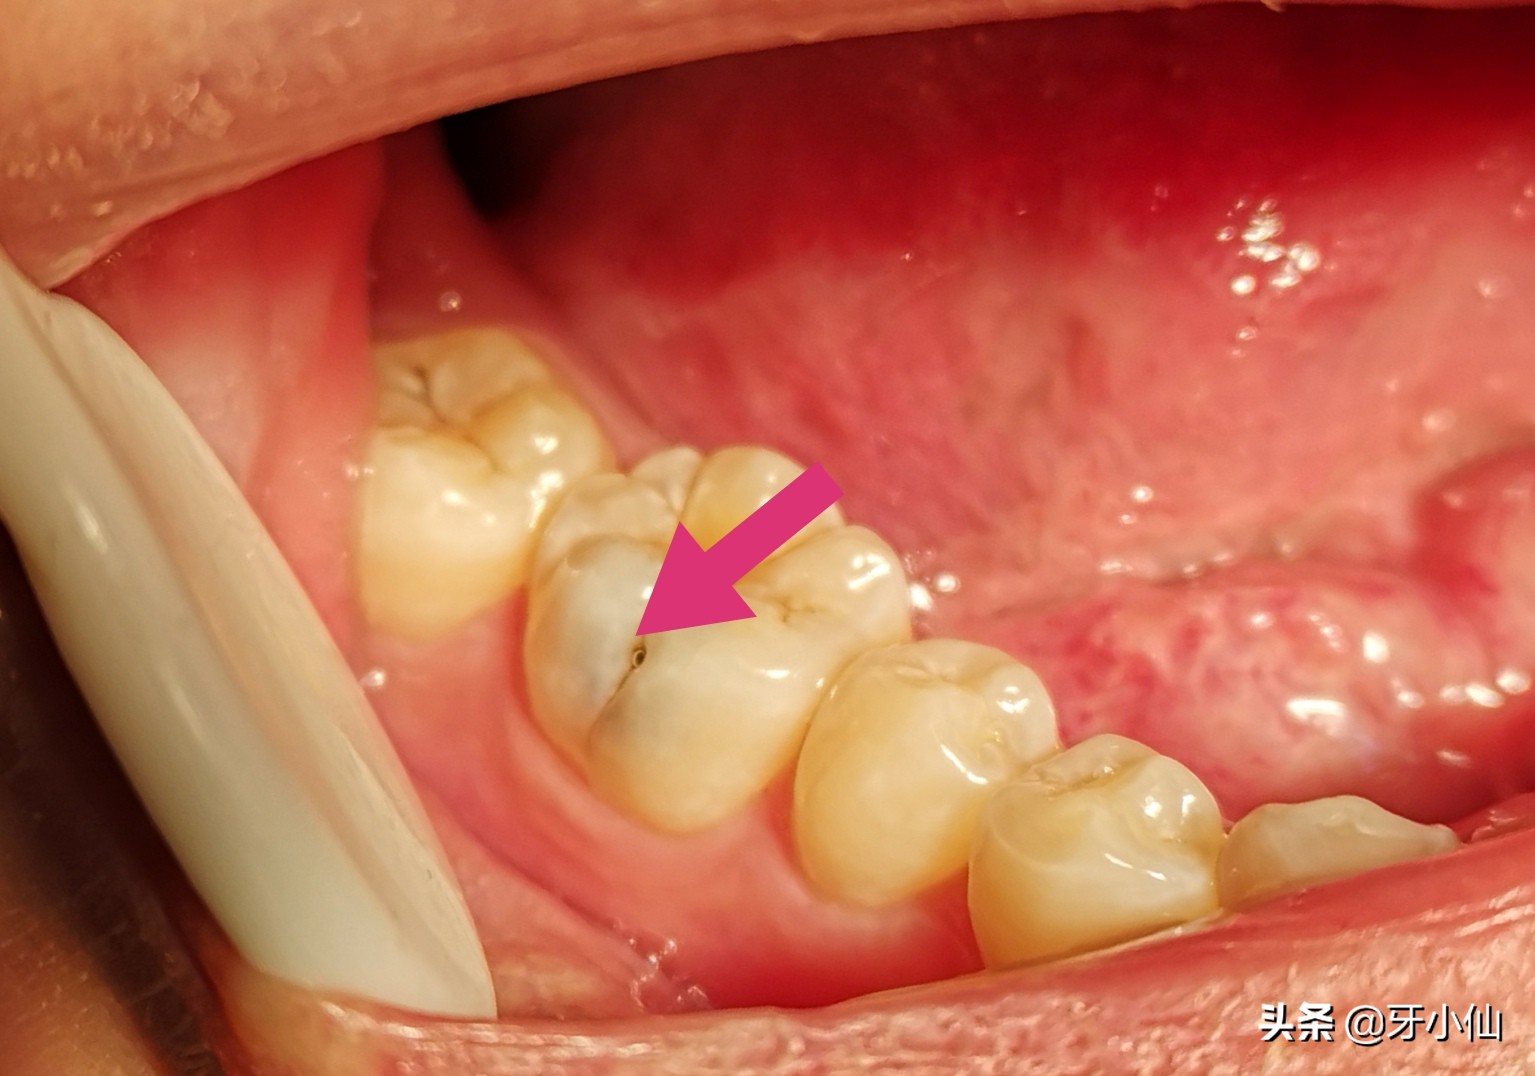

如上图所示,因为牙齿侧面长来了一个虫牙(龋齿),虽然表面上看上去只是一个小洞,但是其实里面已经烂得很深了,龋坏组织细菌(虫牙)已经接近到牙髓神经了,牙髓神经能感受到疼痛。

诊断为:深龋(重度虫牙)。

治疗:根据虫牙的具体情况,龋齿充填(补牙);如果烂得很深了,可能根管治疗、冠修复(抽神经,然后包牙套)。